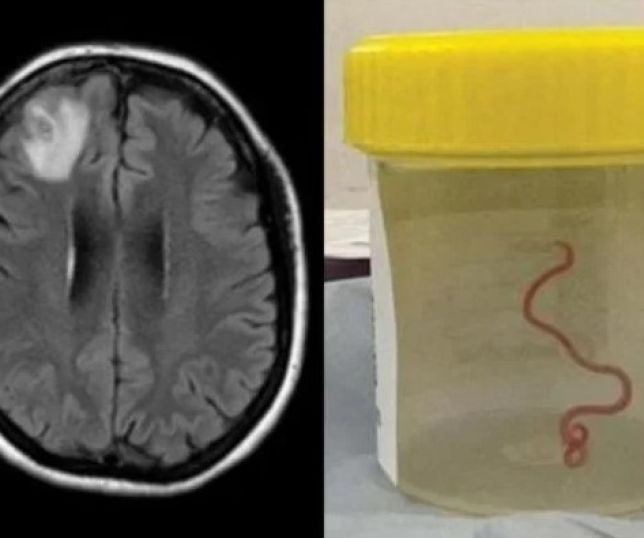

Verme de 8 cm é encontrado em cérebro humano pela primeira vez